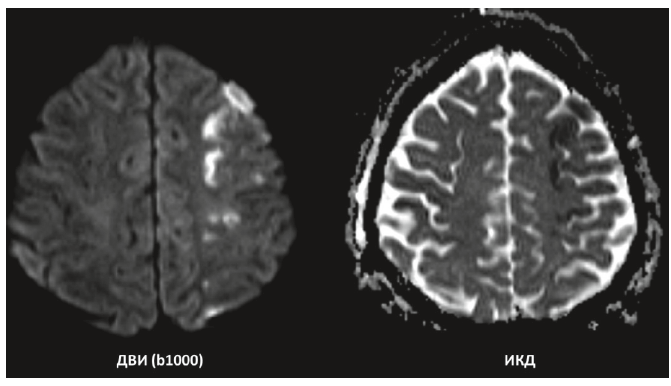

2. Fig. 2. Acute foci of ischemia in patient K., 66 years old, without diabetes mellitus, according to diffusion-weighted magnetic resonance imaging 24 hours after angioplasty with stenting in the cortex of the parietal lobe of the right cerebral hemisphere.